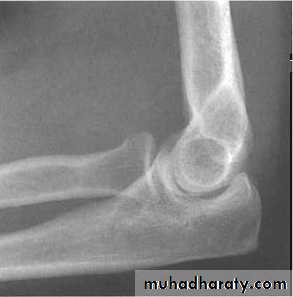

Radiological assessment